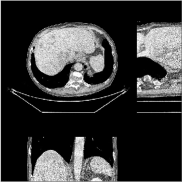

We reconstructed the abdomen volume from low-dose helical CT data. With an initialization of zeros, we ran the PWLS-EP algorithm with and for iterations with subsets for the mA and mA scans, respectively. For PWLS-ULTRA, we chose for the mA scan, for the mA scan, and ran it for outer iterations. The other parameter settings and the transform were the same as those used for the chest scan.

Fig.Β 10 shows the reconstructions (shown for the central axial, sagittal, and coronal planes in the 3D volume) for PWLS-EP and PWLS-ULTRA with patch-based weights () from low-dose abdomen scans. For the sagittal and coronal planes, we show the central out of axial slices. The supplement provides PWLS-EP reconstructions with different regularization strengths. The PWLS-ULTRA reconstructions in Fig.Β 10 have reduced noise as well as higher resolution, better structural details and shaper image edges than the PWLS-EP results. These results are further example of the potential performance of the proposed PWLS-ULTRA method in clinical settings.